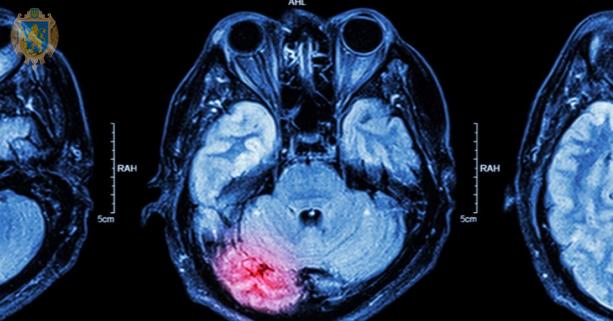

Інсульт - це захворювання, що розвивається внаслідок раптового припинення кровопостачання ділянки головного мозку або крововиливу в речовину мозку чи під його оболонки та стискання тканини мозку кров’ю. Наслідком цього є порушення функціонування та загибель нервових клітин ураженої ділянки, що своєю чергою викликає порушення або втрату функцій тих частин тіла, якими вони керують. Залежно від локалізації ураження, можливе порушення мови, чутливості, рухової функції, зору, пам’яті тощо.